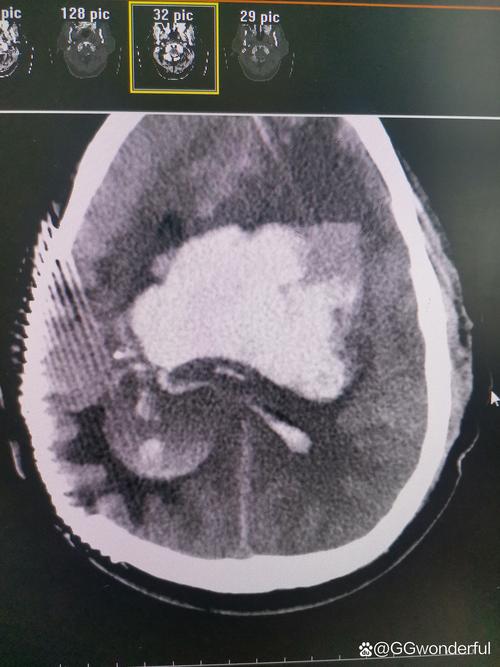

发现术后出血后怎么办?(临床意义和处理原则)

一旦CT确认术后出血,病情的严重程度取决于出血量、出血部位、是否引起中线移位及脑疝。

紧急评估

- 再次手术: 如果出血量大、占位效应明显(特别是中线移位>5mm)、患者意识状态恶化(如GCS评分下降),通常需要立即进行二次开颅手术,清除血肿、彻底止血、缓解颅高压。

- 保守治疗: 如果出血量很小(如<10-15ml)、没有明显占位效应、患者临床症状稳定,可以采取保守治疗。